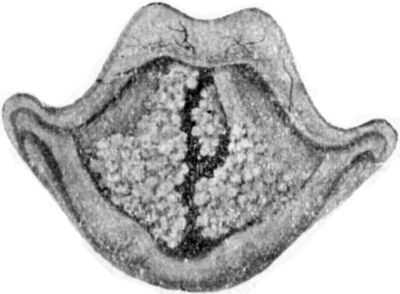

| 161. | Section of Hammer-Toe | 301 |

| 162. | Congenital Hypertrophy of Left Lower Extremity in a Boy | 302 |